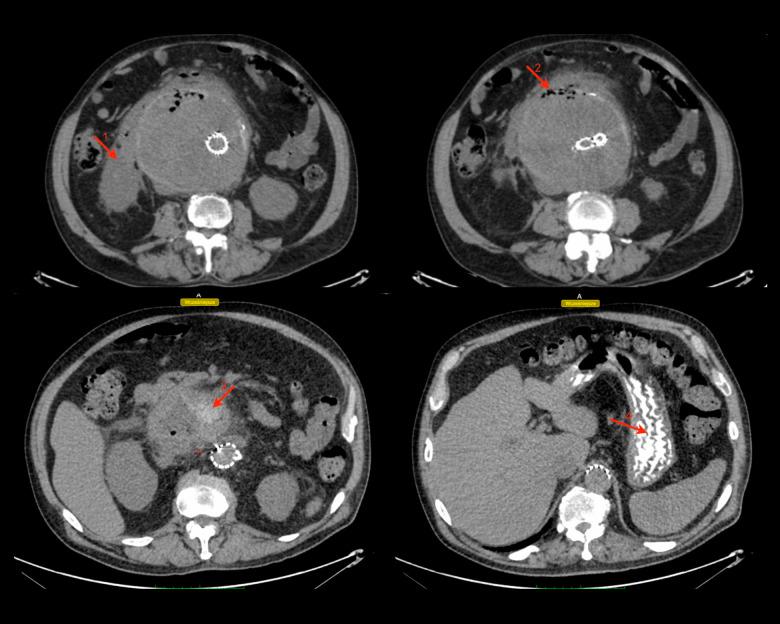

BACKGROUND Aorto-duodenal fistula (ADF) is a communication between the aorta and the duodenum and requires urgent aortic repair. However, it often leads to life-threatening complications. Thus, an early and appropriate diagnostic method is necessary to deliver adequate treatment. This report describes the case of a 68-year-old man with anaorto-duodenal fistula following emergency endovascular repair of a 14-cm abdominal aortic aneurysm (AAA) identified using oral contrast computed tomography (CT), and discusses the consequences of delayed treatment and ADF management. CASE REPORT We present a case of a 68-year-old White man with abdominal bloating, who upon further examination was diagnosed with an AAA, which was successfully treated by endovascular aneurysm repair (EVAR). However, 1 year later, an endoleak was discovered and, despite the physicians' efforts, the overall treatment was complicated due to the patient's continuous postponement of treatment over several years. The aneurysm continued to expand until it reached 14 cm. Despite the successful endovascular repair of the endoleak, a duodeno-aortic fistula (DAF) was diagnosed using CT with oral contrast. The patient was managed conservatively with aneurysmal sac drainage and antibiotic therapy, which decreased the size of the aneurysmal sac. Despite early diagnostic efforts and interventions, the patient's condition deteriorated due to further complications, ultimately resulting in death. CONCLUSIONS This case report demonstrates a potential useful diagnostic role of CT with oral contrast in detecting DAF, in situations when other methods fail to do so, and emphasizes the importance of prompt intervention to prevent life-threatening complications. However, further investigations to explore the underlying mechanism and its replicability are required.

背景 主动脉十二指肠瘘(ADF)是主动脉与十二指肠之间的连通,需要紧急进行主动脉修复。然而,它常常导致危及生命的并发症。因此,需要一种早期且合适的诊断方法来进行充分治疗。本报告描述了一例68岁男性患者,在使用口服对比剂计算机断层扫描(CT)确诊为14厘米腹主动脉瘤(AAA)并进行紧急血管内修复后发生主动脉十二指肠瘘的病例,并讨论了延迟治疗的后果及ADF的处理。病例报告 我们报告一例68岁白人男性患者,有腹部胀满症状,进一步检查诊断为AAA,通过血管内动脉瘤修复术(EVAR)成功治疗。然而,1年后发现内漏,尽管医生努力,但由于患者多年来持续推迟治疗,整体治疗变得复杂。动脉瘤持续扩大直至达到14厘米。尽管成功进行了内漏的血管内修复,但通过口服对比剂CT诊断出十二指肠主动脉瘘(DAF)。患者接受了动脉瘤囊引流和抗生素治疗的保守治疗,这减小了动脉瘤囊的大小。尽管进行了早期诊断和干预,但由于进一步的并发症,患者病情恶化,最终导致死亡。结论 本病例报告表明,在其他方法无法检测到DAF的情况下,口服对比剂CT在检测DAF方面具有潜在的有用诊断作用,并强调了及时干预以预防危及生命并发症的重要性。然而,需要进一步研究以探索其潜在机制及其可重复性。